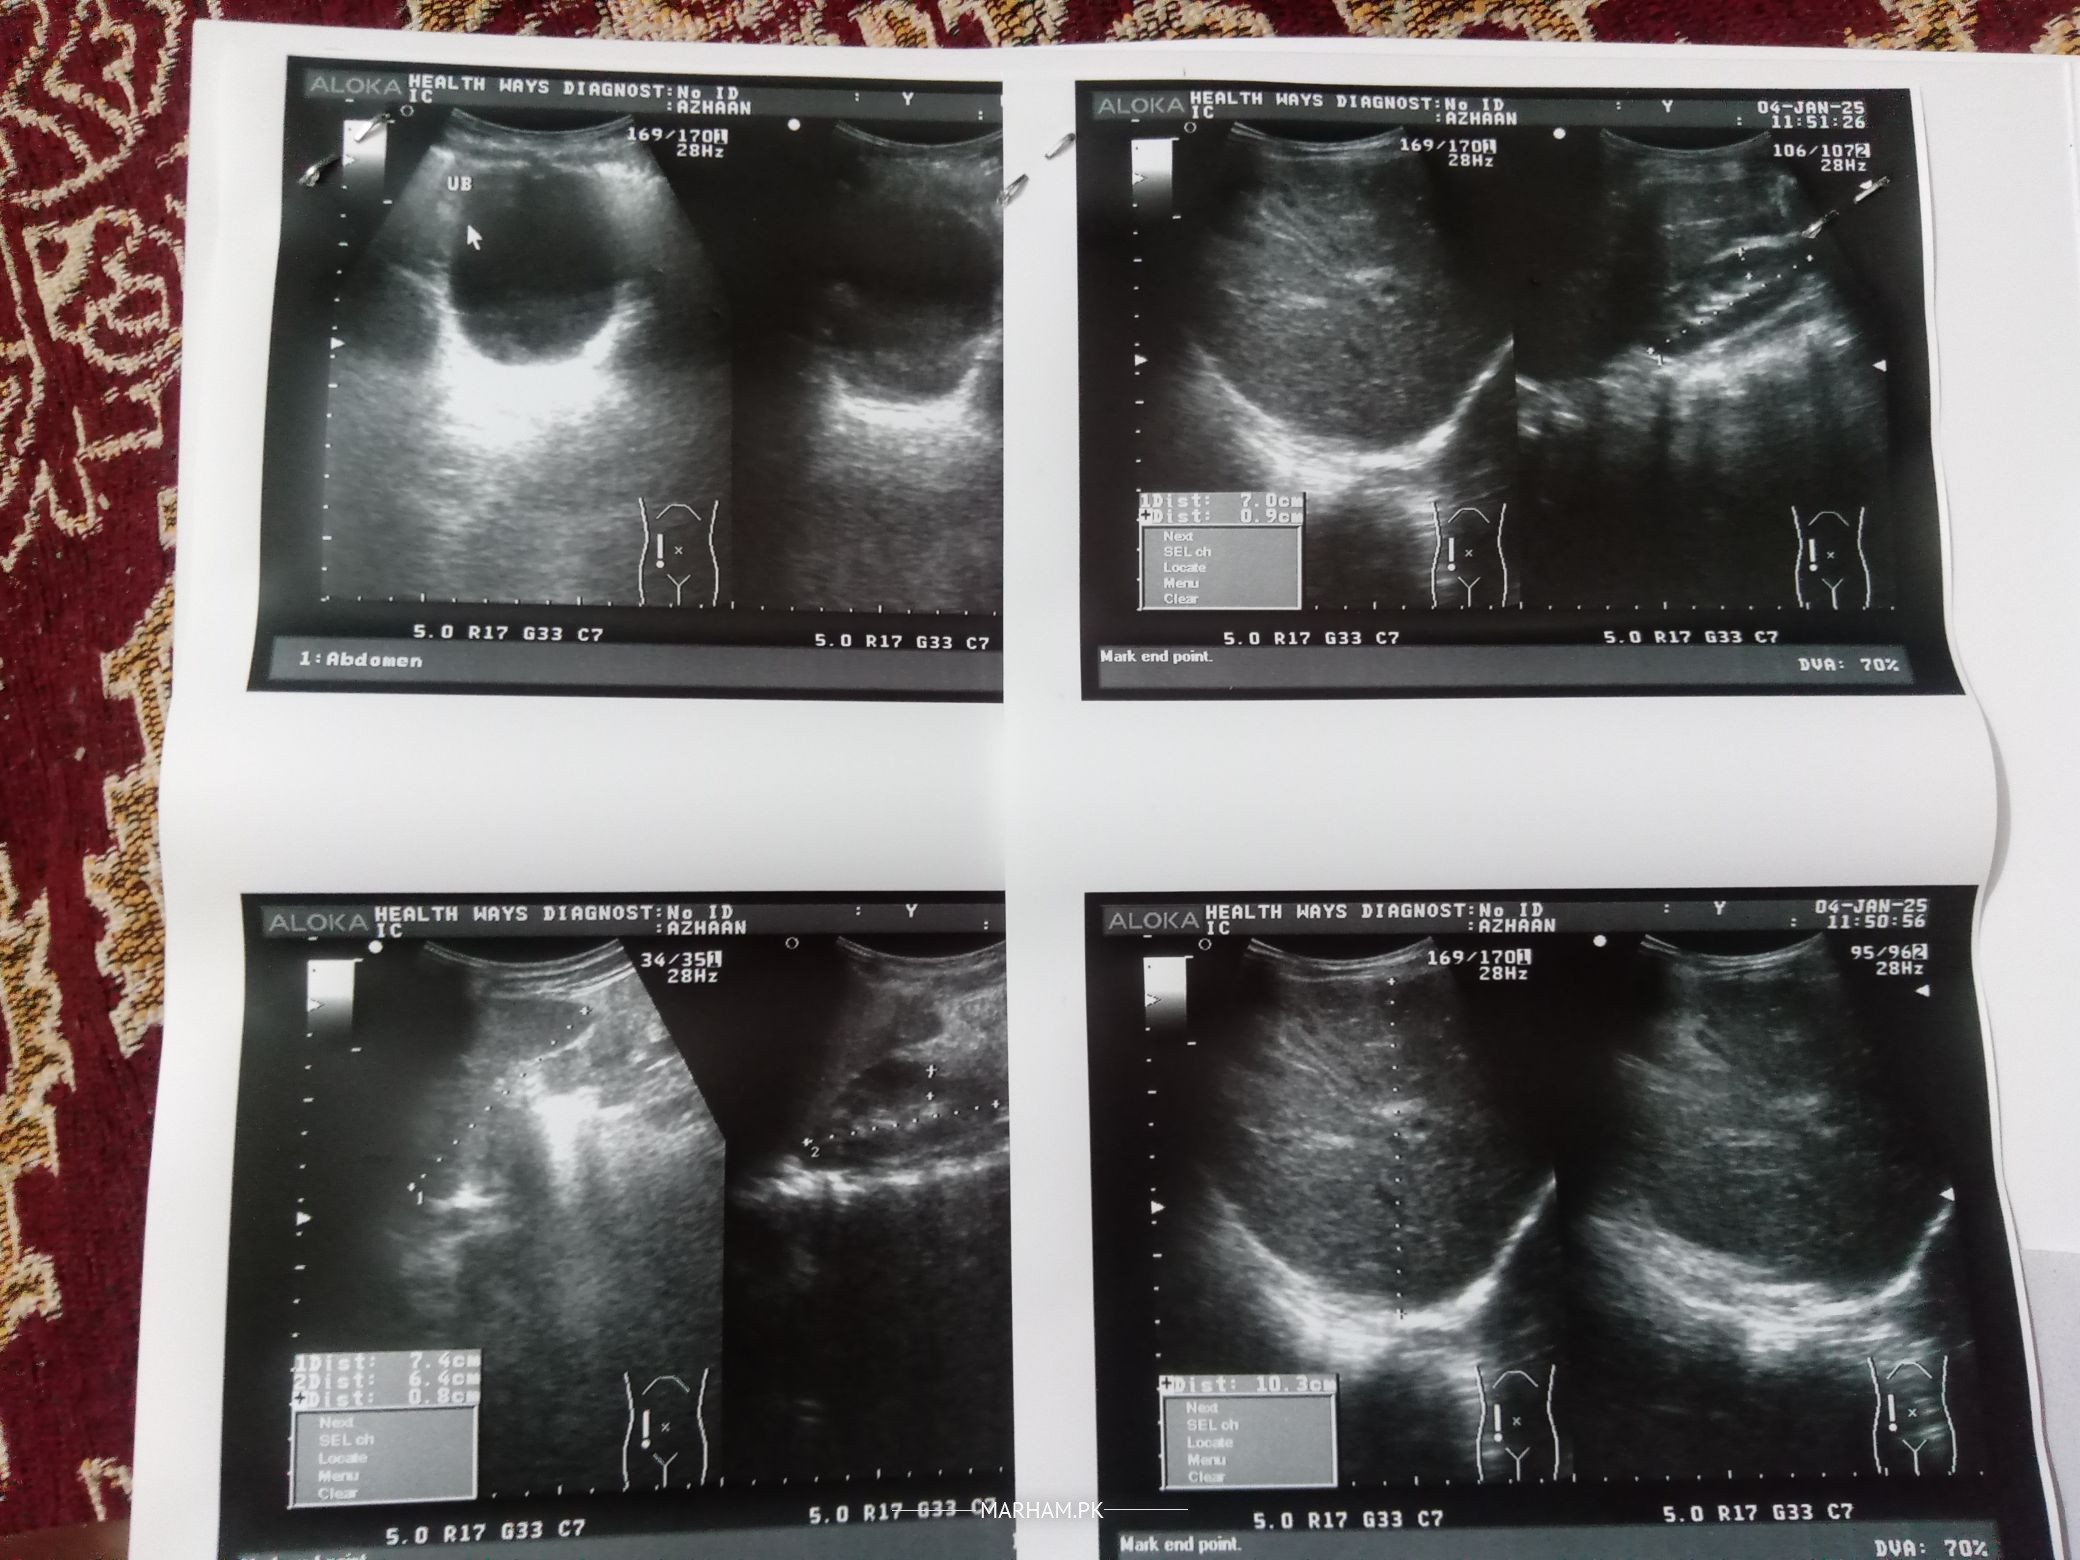

Asalamualykum I want Experienced Opinion. My son is 4 years 2 months old, I'm also attaching his ultra sound reports about inguinal hernia. Is it only Curable With Operation? or I should wait for couple of weeks to check if it heals by its own.

But now from the past 3 days I can see swelling on the right side above scrotum. Today I went to Cantonment Hospital RWP cantt and General surgeon told me after checking the ultrasound reports that we will operate it.